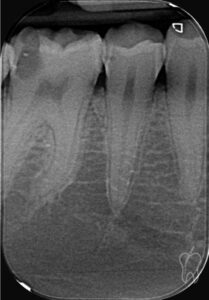

No obstante, para instrumentar adecuadamente los conductos mesiales, que suelen presentar una angulación marcada, se generó un segundo acceso conservador o acceso mesial, proyectado sobre la zona donde emergen los orificios MV y ML (Figura 2)

Figura 2

Este enfoque corresponde al denominado acceso Truss (Figura 3), que mantiene:

• El puente dentario central.

• Parte de la superficie oclusal intacta.

• Mayor resistencia estructural, especialmente en áreas críticas.

Figura 3

A continuación, se permeabilizaron los conductos con limas Pre-K (Endogal) y se procedió a una preinstrumentación rotatoria con 15/03 (Figura 4).

Figura 4